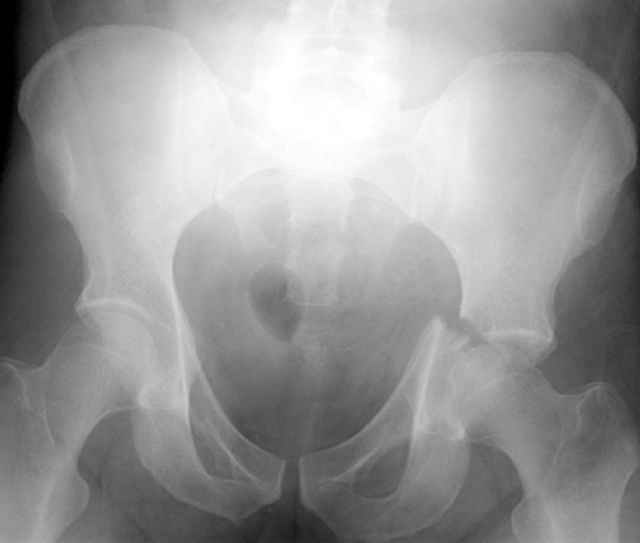

I'll include a few images of a similar injury in a similarly large male patient. This patient "showed up" in our ER c/o hip pain 2 months after being treated in the lateral position, without a quality reduction, without an anterior column transverse supporting implant, with an unbalanced plate applied too medially, with insufficient caudal segment fixation...it took over 8 hours and a 3+ l blood loss to debride the callus from front then

back, excise the HO, release his sciatic nerve, reduce the head-transverse-wall, and fix it...and now it's a staging procedure.

The 2nd example is of a motorcyclist with a transverse fracture-dislocation...he had a closed attempted reduction and placed in traction but the manipulative reduction was not concentric (not unusual for this injury pattern)...so the traction was adjusted to be just enough to disengage the head from the fracture (12#) until he could be cleared for surgery one day after injury...he was treated "urgently" then with a prone KL, clean the fracture, reduce and clamp it, screw it, support with a balanced plate, close, and enjoy...2-3hours, 400cc EBL, blah, blah, blah..